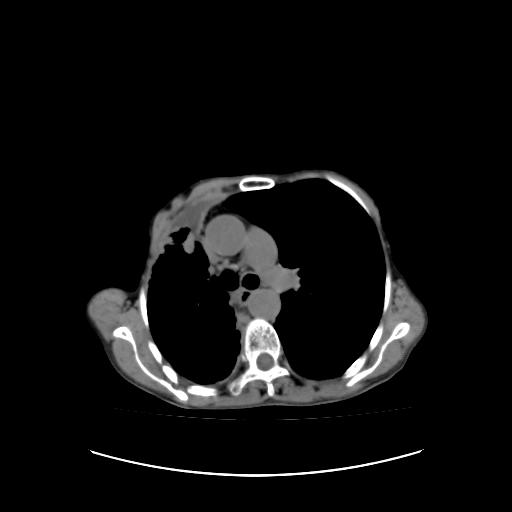

标题: CT16930:女 59 胸痛6个月 胸水脱落细胞学见瘤细胞 [打印本页]

标题: CT16930:女 59 胸痛6个月 胸水脱落细胞学见瘤细胞

可见多发肺内病灶,且胸膜病灶较多有圆球状而非丘状,多考虑胸膜转移瘤伴胸腔积液,右侧胸廓缩小固定,且部分病灶呈丘状,尚不除外恶性胸膜间皮瘤伴肺内转移

右侧胸膜增厚,局部呈结节状增厚,右侧胸腔少量积液。双肺未见确切肿块影。纵隔未见淋巴结肿大。气管、支气管通畅。考虑右侧胸膜间皮瘤(恶性?)可能性大。不除外癌性胸膜炎。

恶性胸膜间皮瘤伴肺内转移可能性大;或胸膜、肺内均为转移瘤,左肺下叶亦见多发小结节影。

右侧胸廓塌陷,右侧胸膜广泛增厚并见多发胸膜结节,右侧少量胸腔积液并包裹。

右侧广泛胸膜增厚,局部呈结节状增厚,右侧胸腔少量积液。双肺未见确切肿块影。纵隔未见淋巴结肿大。气管、支气管通畅。考虑右侧胸膜间皮瘤(恶性?)可能性大。支持!

右侧胸膜转移瘤,原发灶可能就在在右肺,另外建议检查右侧乳腺.

右胸腔结节均考虑来自胸膜(部分来源于叶裂),考虑胸膜间皮瘤或转移瘤.